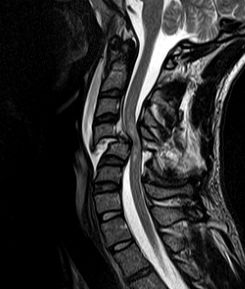

Back pain is the most common problem, people seek medical advice. When one talk about back pain, its mean pain that originates in the spine anywhere between the upper and lower back.

Treatment for back pain varies from medicines, physiotherapy, spinal injections to Spine Surgery. Majority of the patients recovered without operative treatment, only few of them require surgery.

Lumbar Radicular Pain is Back or neck pain that travels into the leg or arms respectively considered as radicular pain, especially when it is radiating below the knee and elbow which leads to a condition called sciatica in leg and brachialgia in arms. Commonly the systems are associated with back pain with symptoms such as tingling and numbness sensations, weakness, stiffness and occasionally involvement of bowel and bladder sensation commonly known as “Cauda Equina Syndrome”. It is a serious problem in the spine & an emergency where the pinched nerve roots have to be freed immediately.

Spine surgery deals with any ailment which arises from the affliction of the spinal column, be it the vertebral bodies, the spinal cord or nerves, protruded intervertebral discs or joints.